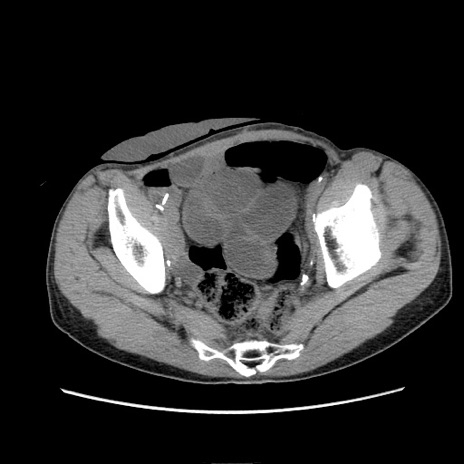

症例11(横断像)

【症例】 60歳代男性

【主訴】 下腹部痛

【現病歴】 本日夜中より下腹部痛の症状認め、受診。

【既往歴】 膀胱癌(膀胱全摘+尿管皮膚瘻術) 、胃癌術後

【身体所見】 BT 35.3℃、PR 58/min、BP 136/98mHg、腹部平坦、軟、腸蠕動音±、ストマ留置あり、左上腹部~正中部に圧痛あり、反跳痛なし。

【データ】WBC 5100、CRP0.01